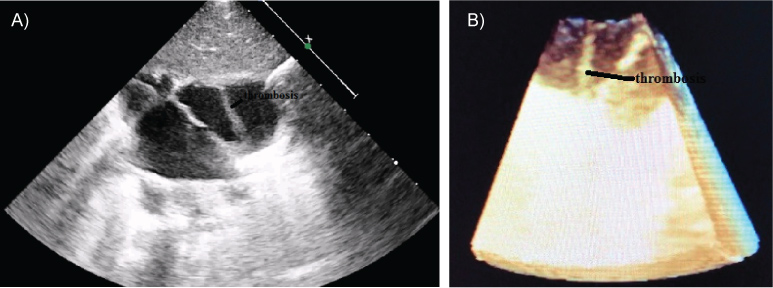

A two-months-old girl suffering weakness, anorexia, vomiting and growth retardation presented to our hospital. She was diagnosed Bartter syndrome. In her history, it was learned that she was hospitalized for sepsis, pneumonia and was cannulated with the umbilical venous catheter. Seventh day of the birth, echocardiography performed due to murmur had no additional pathology other than foramen ovale. In her physical examination, the heart rate was 136/bpm, respiratory rate was 28/min, blood pressure was 85/52 mmHg, and peripheral oxygen saturation was 94% by pulse oximetry. The patient had no dyspnea. There was a 2/6 systolic murmur over mesocardiac area. Complete blood count revealed leucocyte: 14.000/mm3, hemoglobin: 11 g/dl, platelet: 280000/mm3. Hepatic and renal function tests, C reactive protein were in normal ranges and blood cultures were negative. Chest X-ray and electrocardiography were also normal. Echocardiographic (ECHO) examination revealed that foramen ovale was patent with left to right shunting. An echodense fibromuscular membran like a thrombosis with dimensions 23*5 mm and which not obstruct the blood flow, was observed in the right atrium cavity between the right atrium anterior wall and the coaptation area of the tricuspid valve leaflets (Figure 1A and Figure 1B). There was no known familial history of thromboembolic disease and examination for thrombophilia was normal. Factor V Leiden, MTHFRC677T, MTHFR A1298C and the prothrombin 20210 gene mutations were not detected, the prothrombotic work-up, including assessment of antithrombin III, protein C: 0.84 (0.65-1.54), protein S, antiphospholipid antibodies, homocystein, was within normal limits. Human cytomegalovirus infection, another possible cause of neonatal thrombosis was also excluded. We observed that the thrombosis was completely resolved after sixteen day of subcutan enoxaparin treatment with therapeutic dose (2 mg/kg per day, 2 doses) (Figure 2). After complete resolution of thrombosis, it was continued for 3 months with a prophylactic dose (one dose per day).

Figure 2: Two dimensional echocardiographic view after treatment (Original). View Figure 2